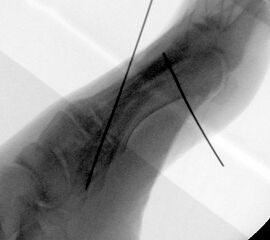

Röntgenaufnahme des Fußes im Stehen im dorsoplantaren und seitlichen Strahlengang (Abb. 1a-b).

Beurteilung des ersten Intermetatarsalwinkels (IMA), des Hallux valgus Winkels (HVA), des distalen (Distal Metatarsal Articular Angle, DMAA) und proximalen Gelenkflächenwinkels der Grundphalanx (Proximal Phalangeal Articular Angle, PPAA).

Abbildung 1a

Abbildung 1b